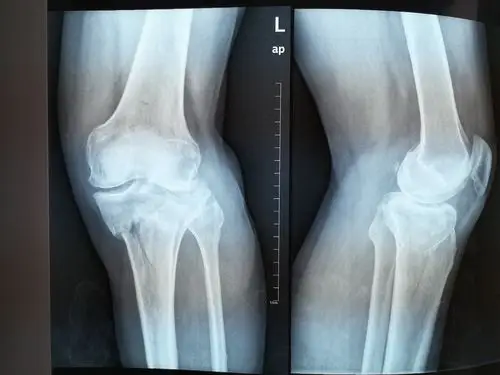

左侧胫骨平台骨折,请看片.